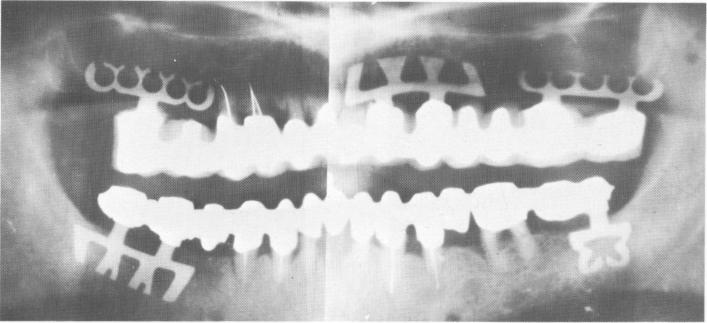

Fig. 15-37. The final Panorex.

2 Final panorex of endosseous upper and lower blade implants in position